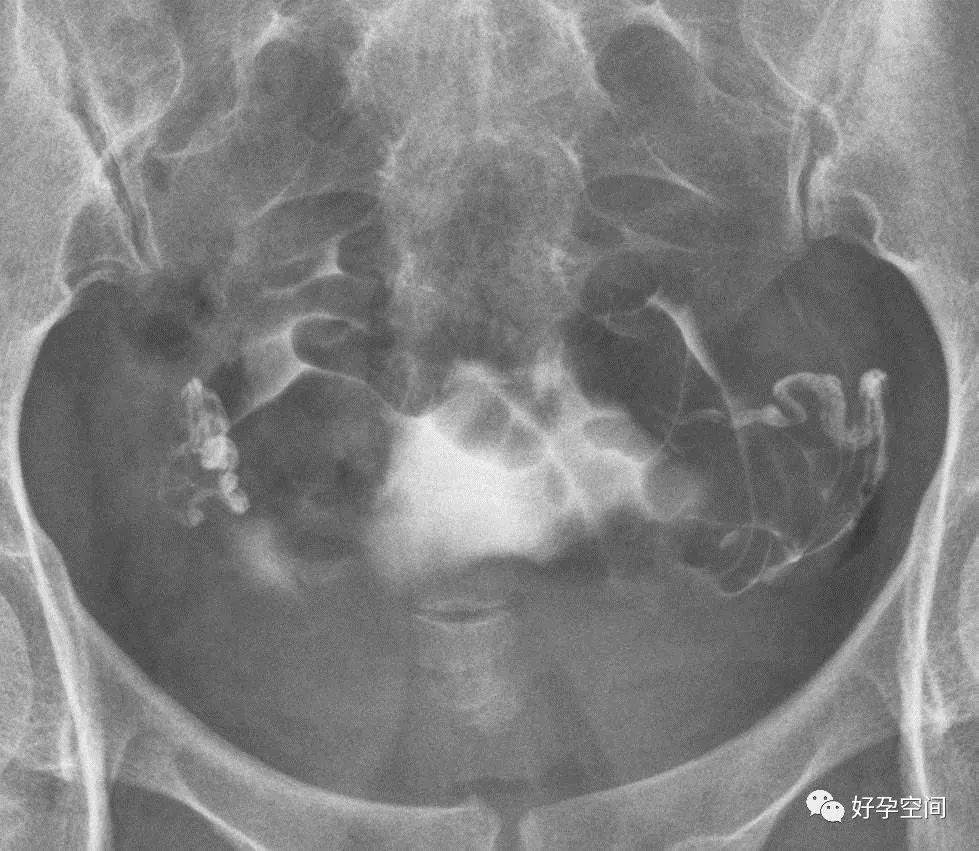

弥散相,延迟5分钟摄片,双侧输卵管内可见较多造影剂

弥散相,延迟10分钟摄片,双侧输卵管内可见少量造影剂

弥散相,延迟20分钟摄片,双侧输卵管内基本没有造影剂残留